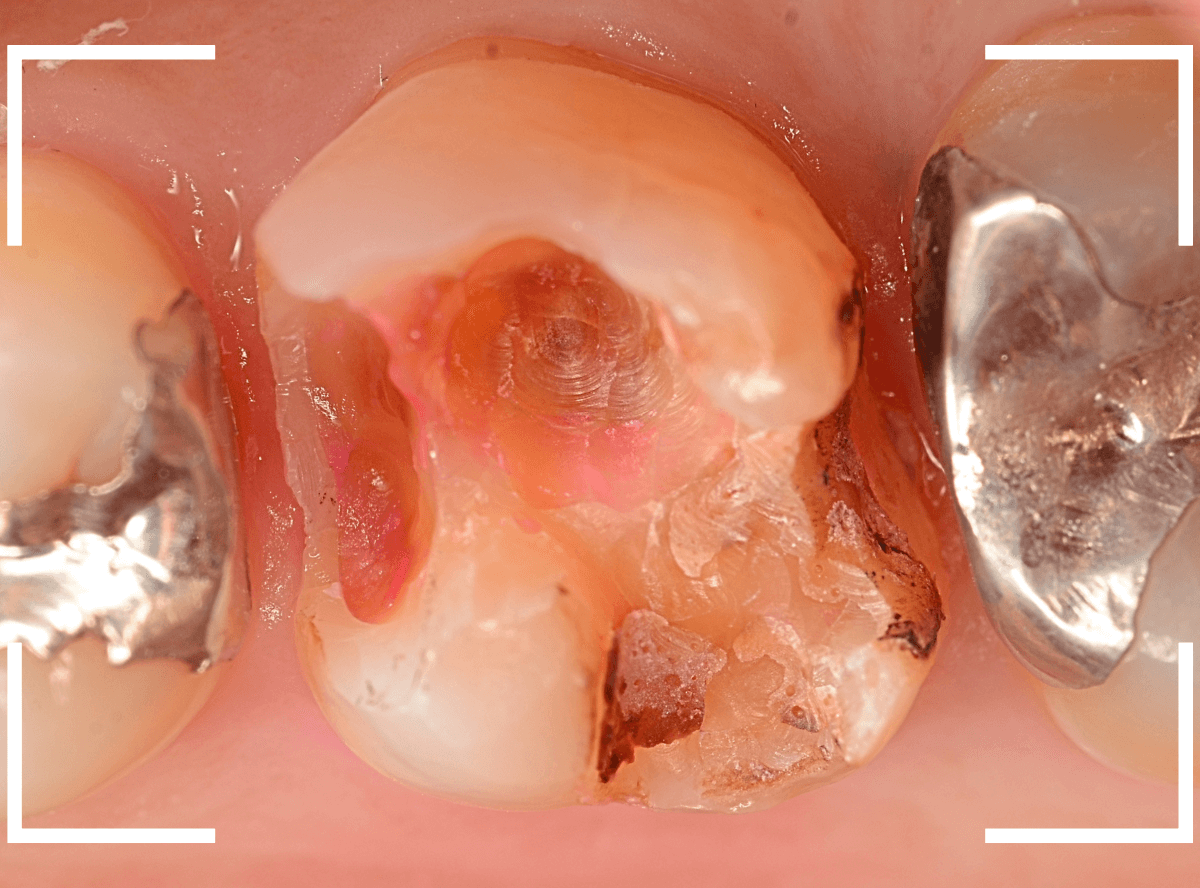

Case.15 歯の側面のレジンの中のわかりづらい虫歯

検診で、金属のつめ物のの中と、歯の側面に虫歯が見つかった方です。

まずは、手前(左)側の治療です。

こちらが、お口の中を見たところです。

〇部の中に虫歯があると思われます。

今回のように、金属のつめ物やレジン治療をしてある歯の側面の虫歯の診断はわかりづらく、難しいです。

金属のつめ物を外したところです。

この白いセメントの中に虫歯があると思われます。

セメントを除去したところです。

赤く染まっている部分が虫歯です。

真っ赤ですね(^^;)

まだ薄く染まっています。

もう少し除去する必要があります。

全ての虫歯が取れました、かなり深い神経まで近い虫歯でした。

金属のつめものをを外します。

つめものの下で虫歯になっていたせいで、虫歯と一緒に手前側のエナメル質がガリっと欠けてきました(><)

前の治療でつめたセメントを外しつつ、虫歯治療を行います。

写真ではわかりづらいですが、赤く染まった部分を中心に、虫歯がかなり広がっています。

虫歯を全て取り切ったところです。

神経スレスレの部分まで広がった虫歯で、最後は神経に触らないようにエキスカを使った、手探りでの虫歯治療になりました。